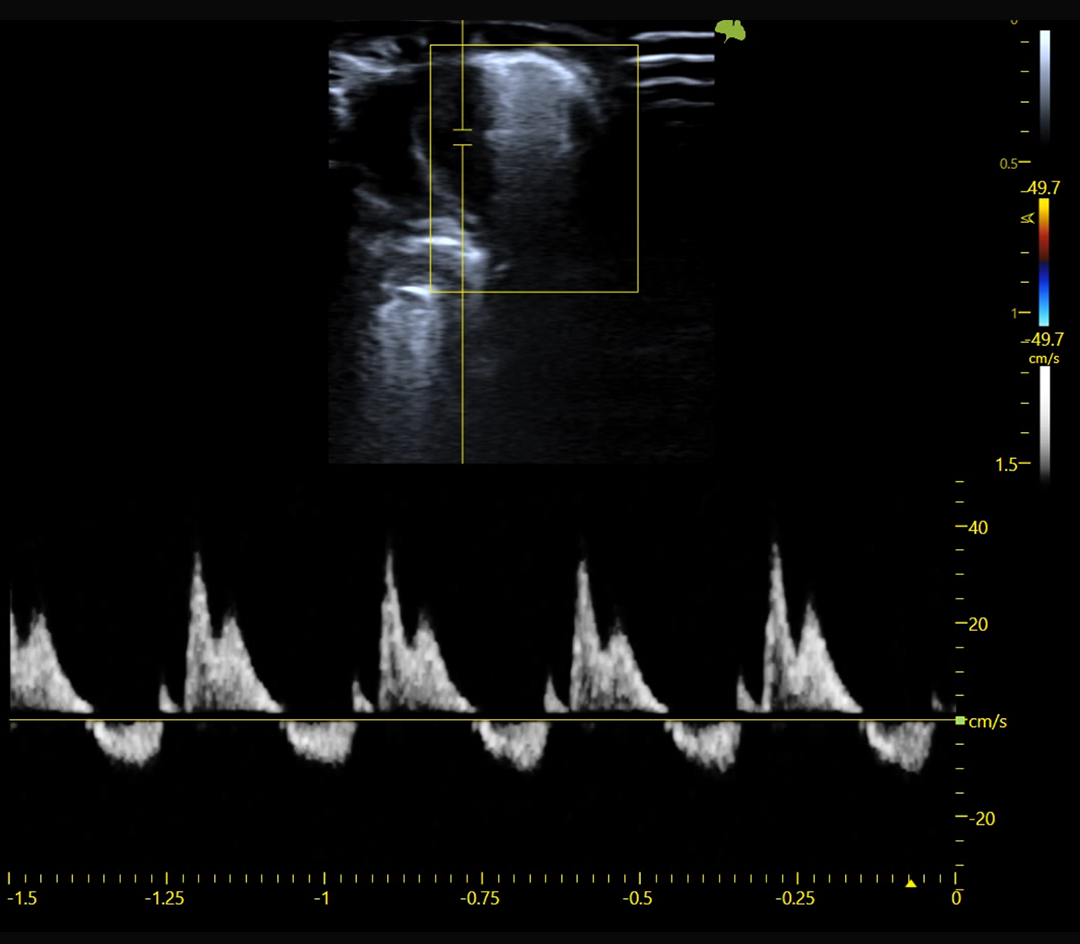

Hémodynamique et flux sanguins

Doppler couleur, pulsé et puissance

Doppler couleur, Doppler pulsé et Doppler puissance

Fonction systolique et diastolique